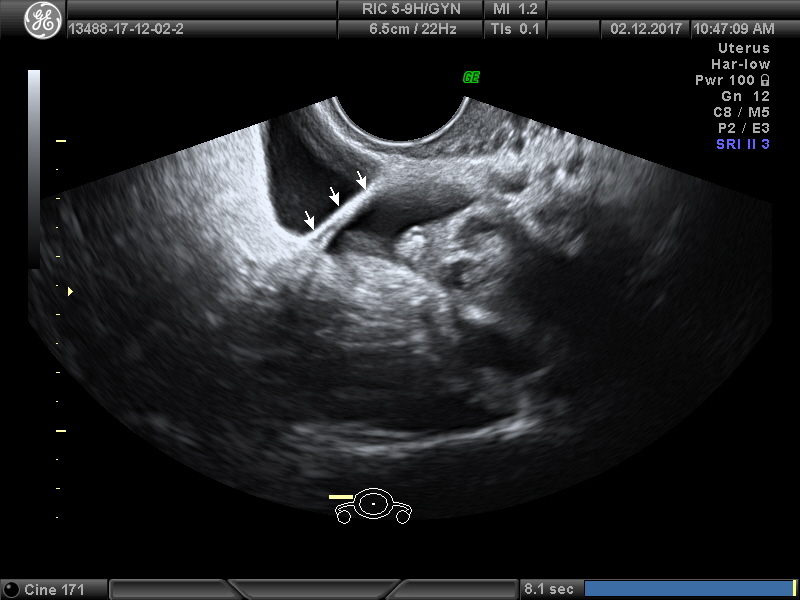

Основной метод исследования при подозрении на СПКЯ — гинекологическое УЗИ матки и придатков.

Во время исследования врач УЗИ-диагностики видит такую картину:

- значительно увеличенные в объёме яичники, иногда их размер почти вдвое больше нормы;

- количество дозревших фолликулов — более 10, все они хорошо просматриваются на УЗИ и имеют диаметр свыше 1 см;

- капсула каждого яичника заметно утолщена.

Уже в ходе УЗИ грамотный врач может отличить проявления поликистоза от признаков мультифолликулярных яичников, которые могут наблюдаться в некоторые фазы цикла и не являются патологией.